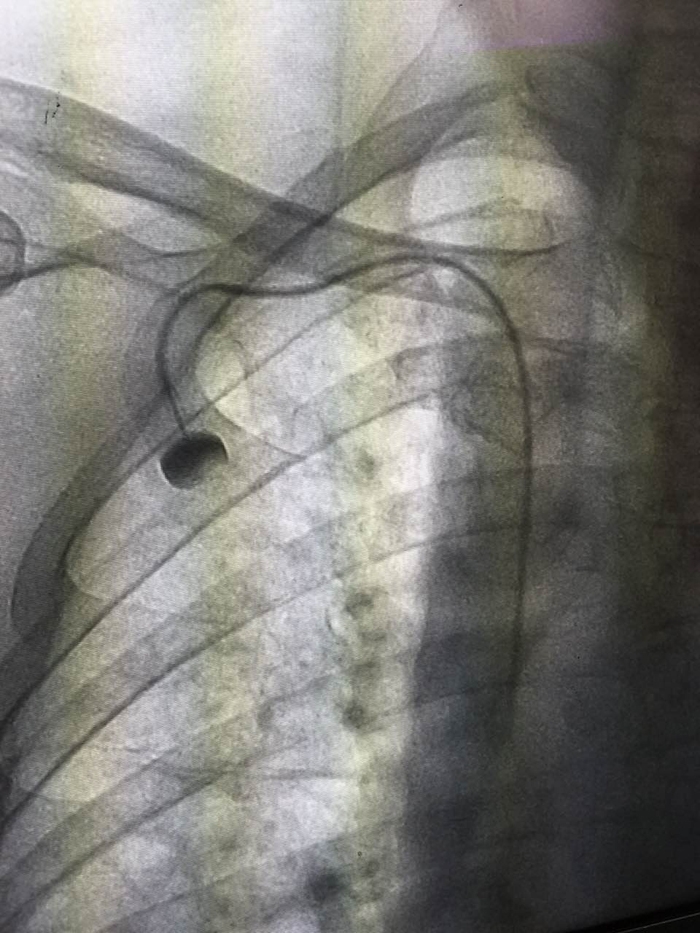

“靜脈輸液港”的X影像

??? 2月26日,我院腫瘤內(nèi)科成功開展了首例植入式靜脈輸液港技術(shù),僅在患者胸部皮膚下植入一枚紐扣大小的“靜脈輸液港”,便可解決患者因反復(fù)輸液導(dǎo)致無血管可扎或長期輸液導(dǎo)管留置的問題。

??? PORT(輸液港)是一種較新的輸液管路技術(shù),是埋植于人體內(nèi)的閉合輸液系統(tǒng),主要由供穿刺的注射座和靜脈導(dǎo)管系統(tǒng)組成。利用小手術(shù)方法將導(dǎo)管經(jīng)皮下穿刺置于人體大靜脈中,如鎖骨下靜脈、上腔靜脈,部分導(dǎo)管埋藏在皮下組織,將另一端的穿刺座留置在胸壁皮下組織中并縫合固定,手術(shù)后皮膚外觀只看到一個(gè)小的縫合傷口,愈合拆線后病人體表可觸摸到一突出圓球。治療時(shí)將針經(jīng)皮穿刺垂直進(jìn)入到穿刺座的儲(chǔ)液槽,既可以方便地進(jìn)行注射,也可以長時(shí)間連續(xù)輸液和采血,而且適用于高濃度的化療藥物、完全胃腸外營養(yǎng)、血液制品的輸注。輸液港植入后病人的日常生活不受限制,接受藥物治療方便又輕松,可在人體內(nèi)存留使用5年甚至更長的時(shí)間。這種技術(shù)的應(yīng)用對白血病患者、惡性腫瘤患者以及長期需要打針輸液的重癥患者,尤其是此類疾病的兒童患者來說,有著重要的意義。